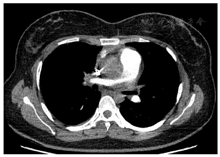

入院查血常规示白细胞计数为10.0×109/L,中性粒细胞比例为59.7%,血红蛋白为93 g/L,血小板计数为479×109/L,平均红细胞体积为71.9 fl,平均红细胞血红蛋白含量23.0 pg,平均红细胞血红蛋白浓度321.0 g/L。尿便常规、肝肾功能、电解质、心肌损伤标志物均正常。超敏C反应蛋白为78.52 mg/L。同型半胱氨酸为10.30 μmol/L。D二聚体为2.32 mg/L。红细胞沉降率为106 mm/h。降钙素原、血尿免疫固定电泳均阴性。直接抗人球蛋白试验弱阳性。抗核抗体阳性(颗粒型1:100),抗ENA谱阴性。免疫球蛋白A 4.5↑ g/L,补体C4 0.376↑ g/L,免疫球蛋白M、免疫球蛋白G和补体C3均正常。类风湿因子、抗环瓜氨酸肽抗体、抗中性粒细胞胞浆抗体、抗肾小球基底膜抗体、狼疮抗凝物、抗心磷脂抗体、抗β2-糖蛋白1抗体均阴性。抗凝血酶活性、蛋白C、蛋白S活性均正常。双下肢深静脉超声未见血栓。超声心动图示左心室射血分数正常,主动脉瓣中度反流,右心室收缩功能正常,肺动脉收缩压正常。肺动脉CT提示右肺上叶前段及右肺中叶肺动脉闭塞,右肺动脉干远端及左肺下叶前基底段肺动脉管腔变窄(图1);右肺中叶远端胸膜下楔形实变灶,尖端指向肺门、周围可见片状磨玻璃影、内可见充气支气管气相(图2);右肺上叶前段胸膜下可见小片状实变灶伴磨玻璃密度;肺实质病变分布位置符合右肺上叶前段、右肺中叶肺动脉供血区域;升主动脉管壁可疑增厚。正电子发射计算机断层显像(positron emission tomography, PET-CT)示升主动脉管壁环形葡萄糖代谢增高,管壁稍增厚、毛糙(图3),考虑大动脉炎可能大。